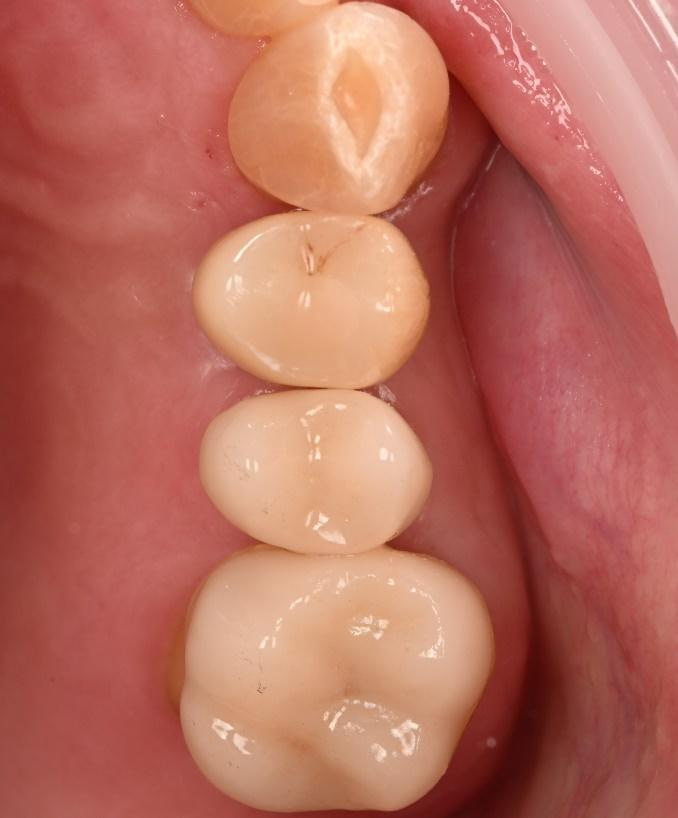

Three months after the implant surgery, a thorough post-operative assessment revealed excellent healing and implant stability.

Digital impressions were captured using the TRIOS 4 intraoral scanner, and the implant-supported crown was designed using 3Shape Design Studio.

The crown was milled from a high-strength, multilayered zirconia and hand-finished to achieve a lifelike appearance.

At the final appointment, the crown was securely attached to the implant, resulting in a beautiful, natural-looking restoration.

The implant-supported crown seamlessly integrated with the patient's natural dentition, and the patient reported excellent comfort and function.